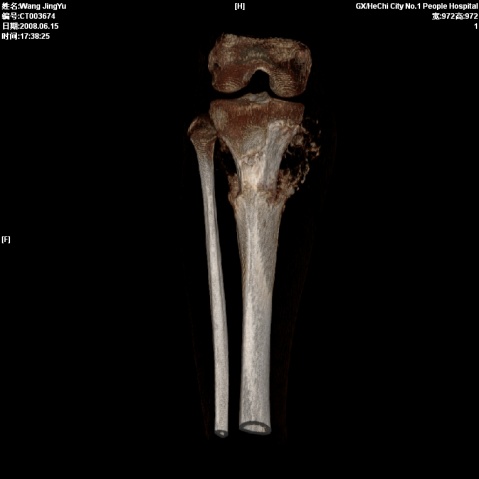

以下是引用随光逐影在2008-6-23 15:30:00的发言:[br]胫骨中上段骨肉瘤(临床表现:好发年龄+好发部位。ct表现:骨质破坏+肿瘤新生骨+骨膜反应并破坏,形成codman氏三角+软组织肿块)。